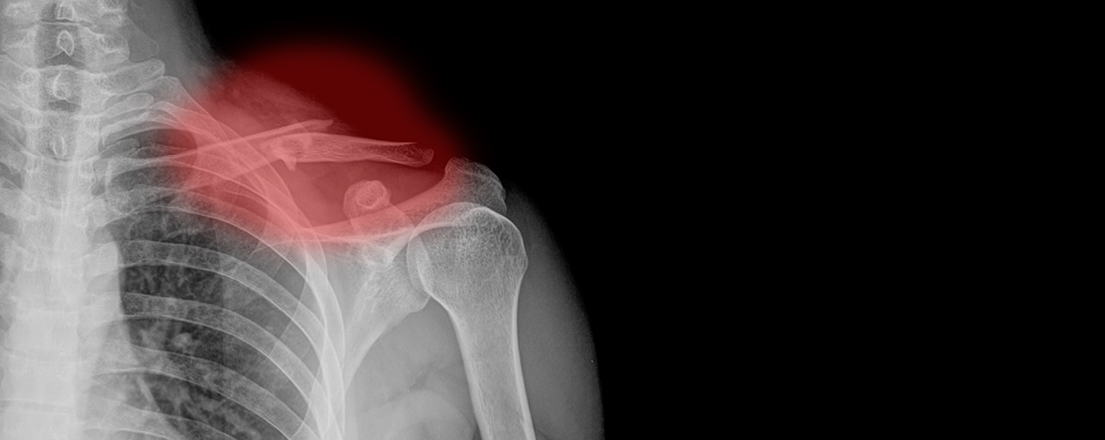

The Silent Threat of Osteoporosis

Osteoporosis is often called a silent disease because it progresses without symptoms until a fracture occurs. Fractures related to osteoporosis are more than just painful; they can lead to significant health complications and a decreased quality of life. Understanding the connection between menopause and osteoporosis is crucial for preventive care.